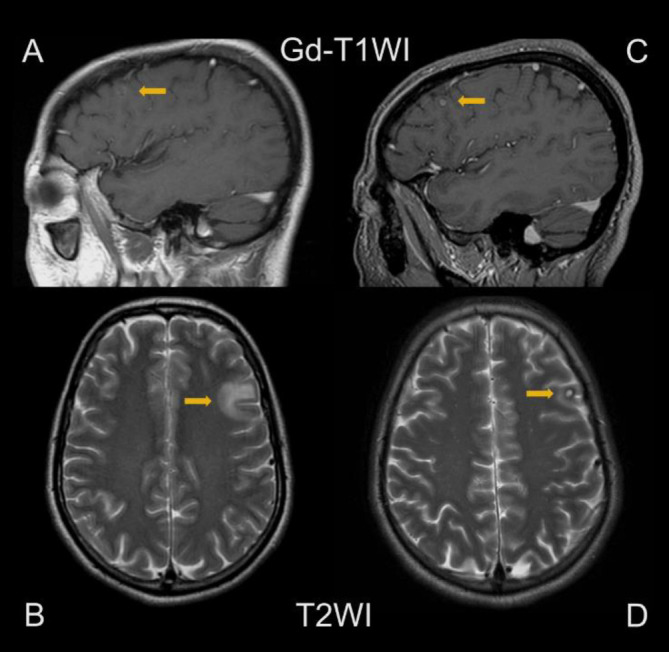

Brain metastasis (BM) occurs only in about 1% of differentiated thyroid carcinoma (DTC) cases. Although DTC generally has a good prognosis, once BM develops, the mortality rate significantly increases up to 78%. BM is usually treated by surgical resection or external radiotherapy, whereas radioactive iodine therapy (RAIT) using I-131 is much less often chosen because BM often shows poor uptake of I-131. In addition, even in case I-131 accumulates in the BM, RAIT could cause adverse effects such as brain hemorrhage and cerebral edema. We present a case of BM from DTC that showed response to I-131 therapy with no severe adverse effects. The brain lesion was very small and asymptomatic, and was only found after a post-therapy I-131 scintigraphy. There are a few case reports where BM was cured by RAIT with little to no side effects. We theorize that BM that is small in size, asymptomatic and show I-131 accumulation could be successfully treated with RAIT.